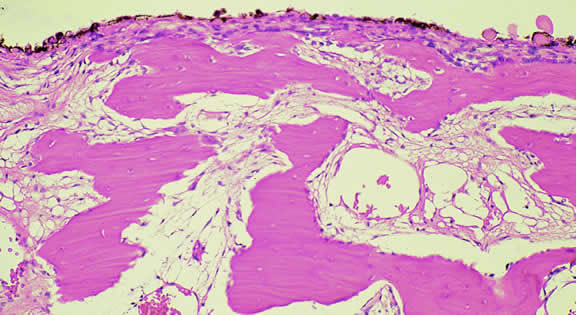

The substrate for the development of melanoma in white patients with ocular melanocytosis is a diffuse nevus that affects all, or part, of the uveal tract. Clinically, the nevus typically is evident as hyperchromic heterochromia iridum, patchy slate gray epibulbar pigmentation, and a darker aspect of the fundus compared with the fellow eye (Fig. 8). A sector of uvea is affected in some patients, however, and the nevus may spare the iris. The uvea in congenital melanocytosis is thickened by an increased number of heavily pigmented nevus cells similar to those found in melanocytomas (Fig. 9). RPE abnormalities such as drusen often develop on the surface of the thickened choroid.48 The sclera also contains patchy foci of pigmentation. The slate gray conjunctival pigment reflects the presence of dendritic melanocytes on the epibulbar tissues deep to the conjunctiva. Nevus of Ota does not predispose to conjunctiva melanoma. However, patients rarely may develop melanomas of the orbit49–51 and even leptomeninges.1,52,53 White patients who have congenital ocular or oculodermal melanocytosis should be followed periodically because of the increased risk of uveal melanoma.54

Fig. 9. Congenital ocular melanocytosis, choroid. Choroidal stroma is thickened by infiltrate of heavily pigmented benign melanocytes. Patient had iris heterochromia and skin pigmentation consistent with nevus of Ota. (Hematoxylin-eosin, × 100.)